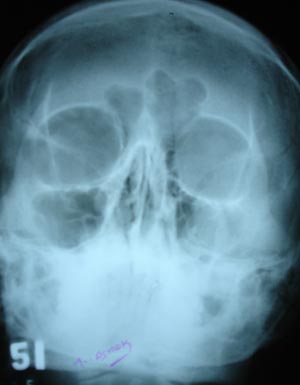

View Maxillary sinusitis

Maxillary sinusitis